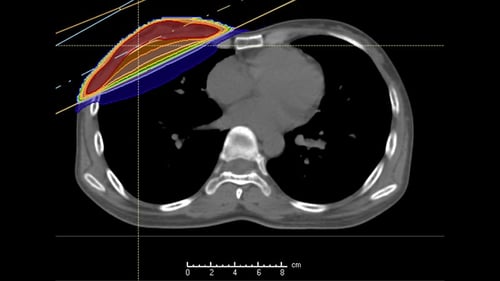

・乳がん

主に手術のあとの術後照射の適応となります。患側の全乳房に対して再発リスクを低減するために放射線治療を行います。腋窩リンパ節転移の有無により同側頚部へも照射することがあります。乳房温存術後の方は17回の短期照射を行っています。乳房切除・腋窩リンパ節郭清後の方は25回の治療となります。切除断端が陽性の場合は5回程度の追加照射を行います。副作用は皮膚炎(発赤、着色、日焼け様症状)、倦怠感、創部皮膚硬結、放射線肺炎(稀:咳、発熱、呼吸苦など)、リンパ浮腫などが起こりえます。(図:乳がんに対する放射線治療)

左乳がんの術後照射には、深吸気息止め照射(DIBH)を行っており、心臓への放射線の影響を低減することが可能です。(上図:DIBHなし 下図:DIBHあり)